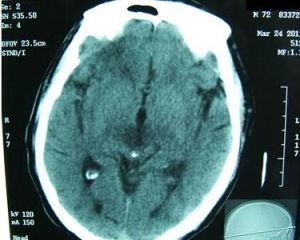

2、顱腦CT檢查 對於有神經系統體徵或併發症可能時,能見到蛛網膜下腔出血,腦室擴大,腦腫脹,硬膜下腔積液,腦膿腫,硬膜外膿腫等表現室管膜炎時腦室周圍低密度異常;